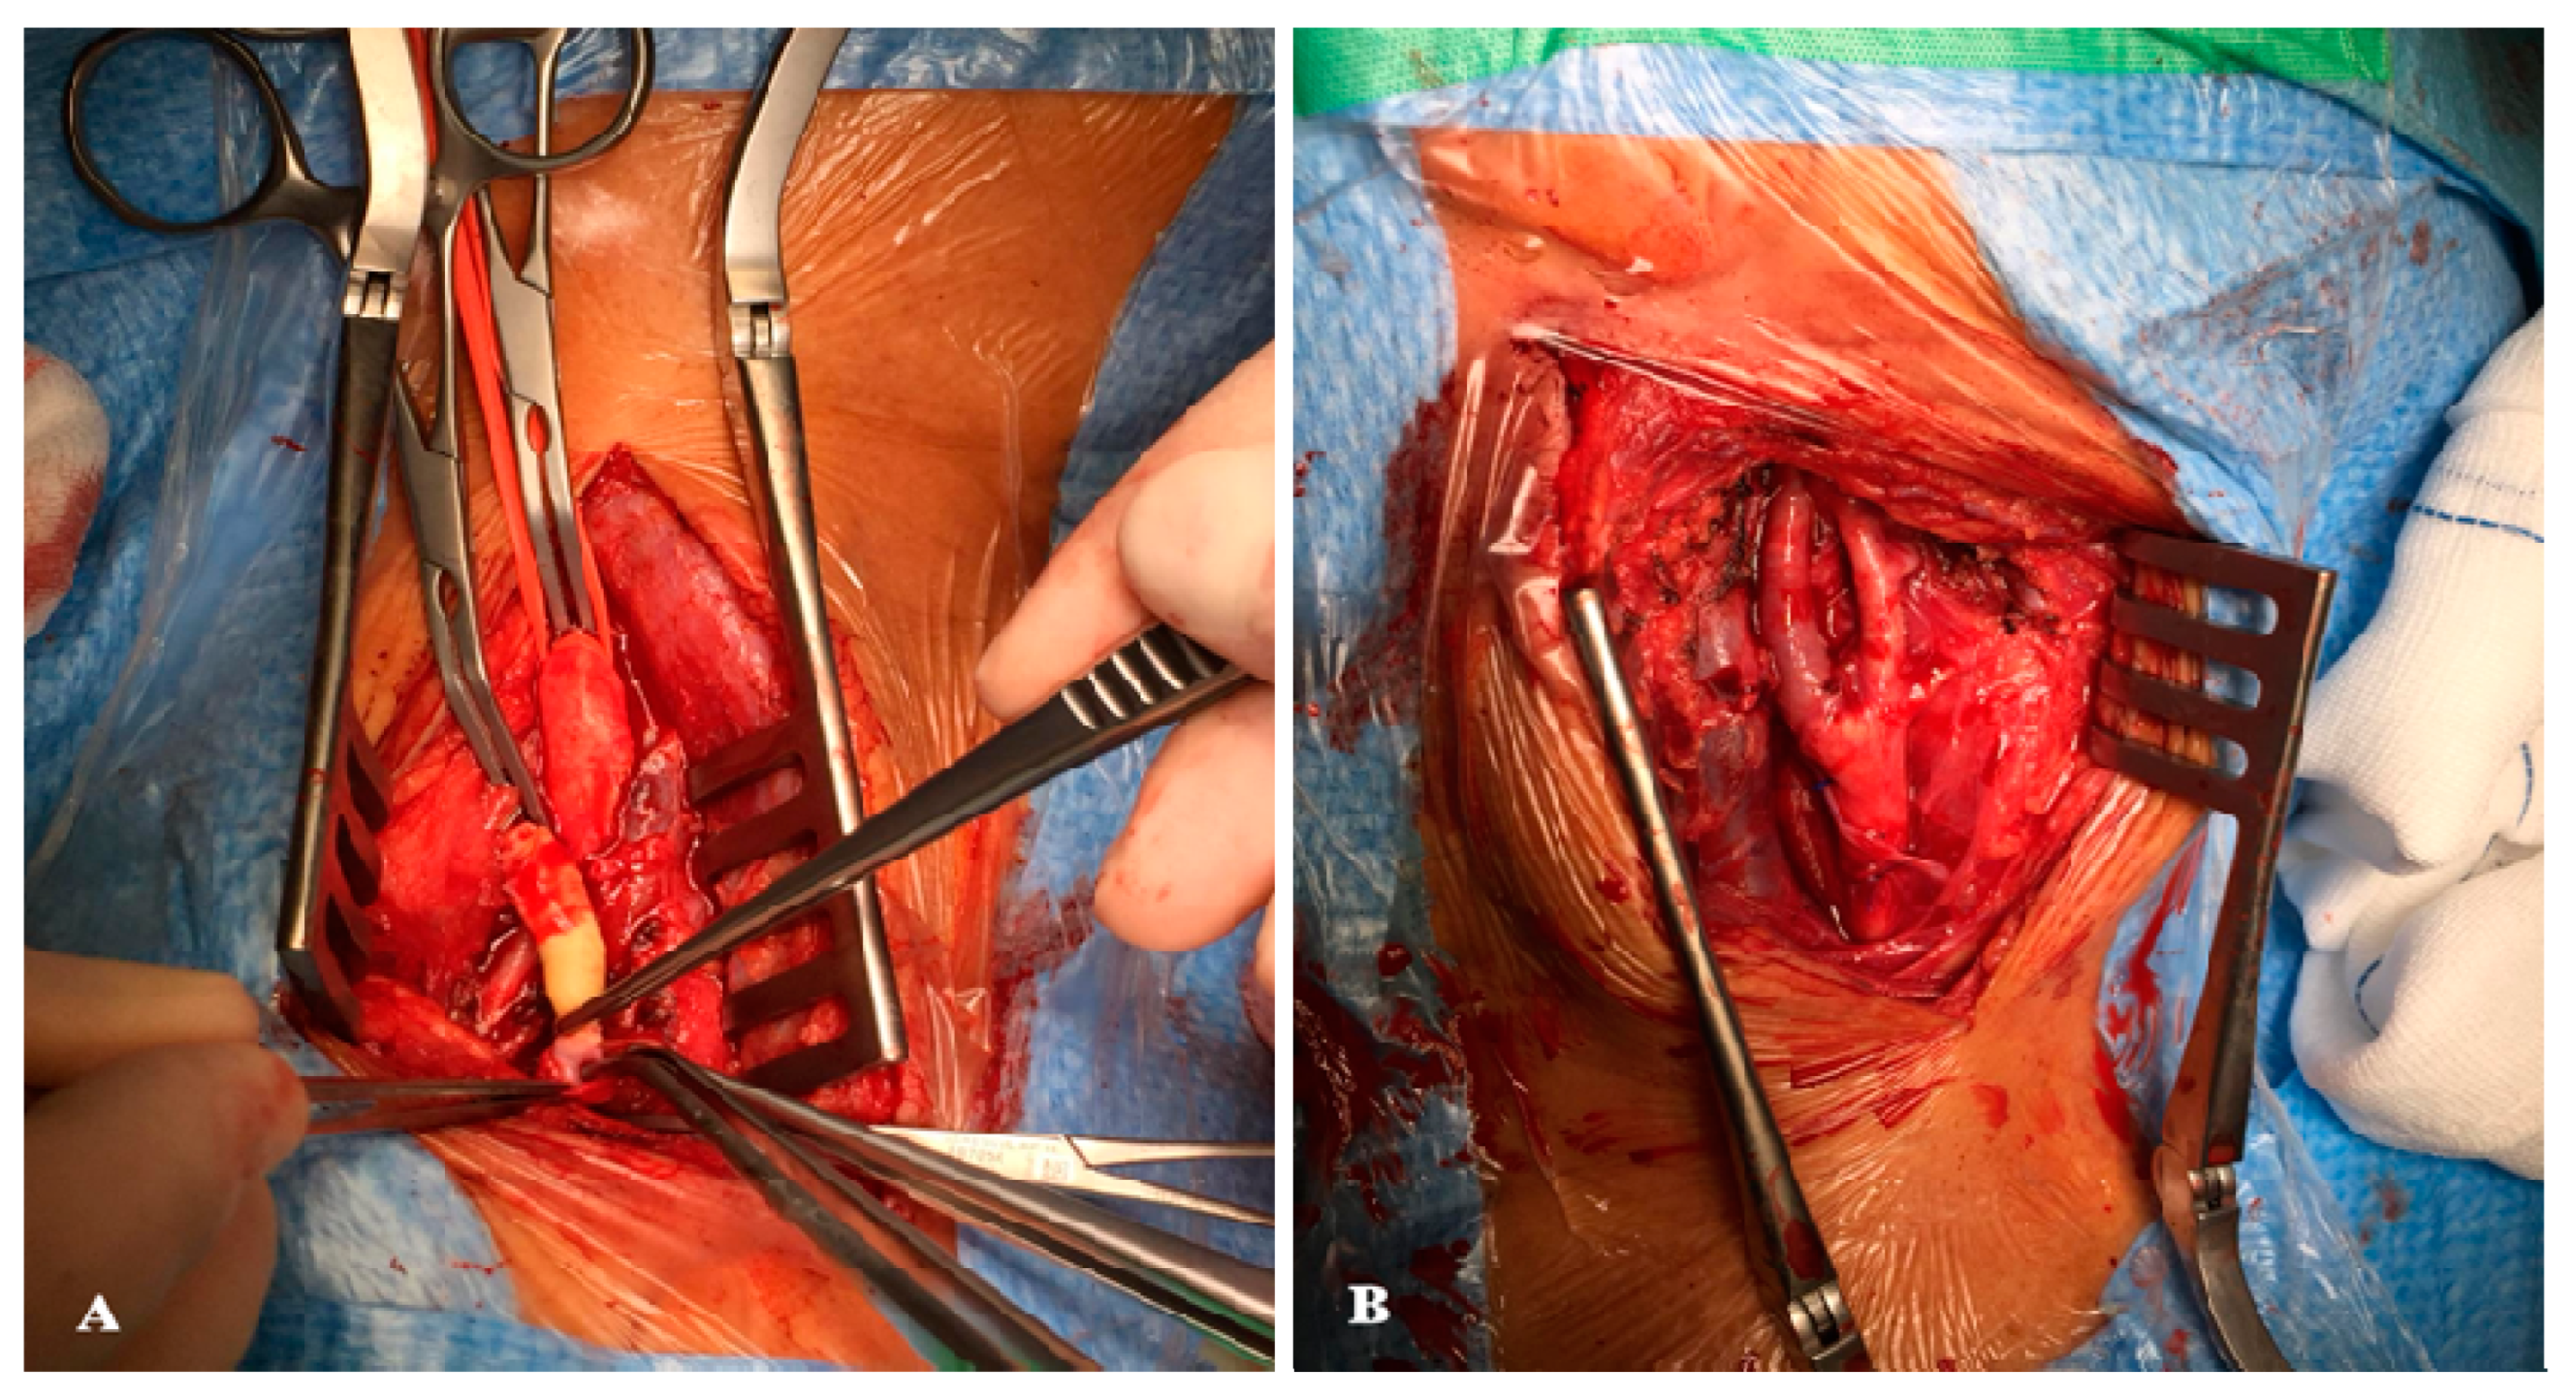

2.2. Surgical Technique